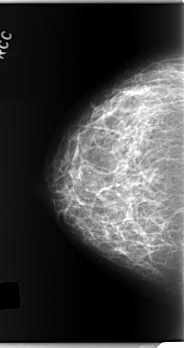

C_0277_1.RIGHT_CC

RIGHT_CC LINES 5904 PIXELS_PER_LINE 3128 BITS_PER_PIXEL 12 RESOLUTION 50 NON_OVERLAY